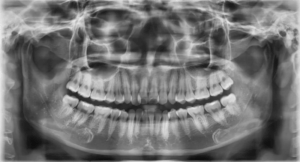

Trước khi tiến hành thủ tục trồng răng implant, việc chụp X-quang là cần thiết để đánh giá tình trạng răng miệng của bạn, bao gồm mật độ xương, tình trạng xương, và các yếu tố khác. Thông tin này sẽ giúp bạn hiểu rõ hơn về khả năng phù hợp của mình cho việc trồng implant cũng như thời gian hoàn thiện quy trình.